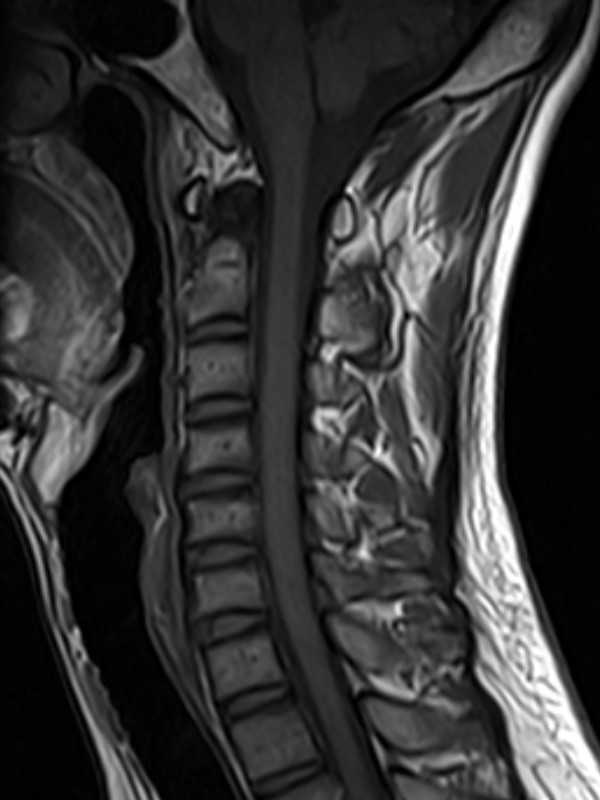

颈椎-STIR